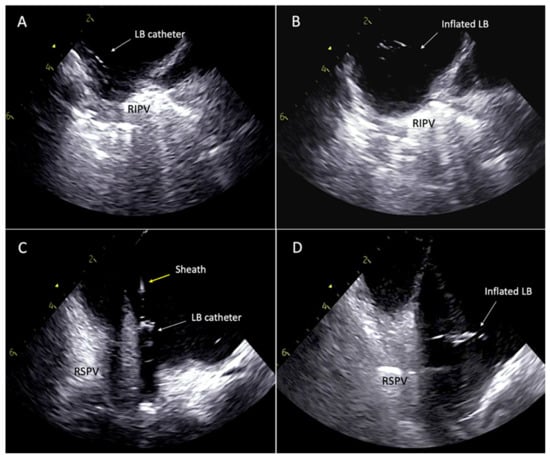

3. Procedural Access

4. Lesion Generation